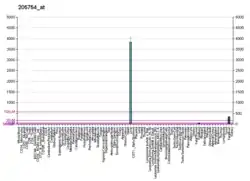

- 1 2 3 GRCh38: Ensembl release 89: ENSG00000180210 - Ensembl, May 2017

- 1 2 3 GRCm38: Ensembl release 89: ENSMUSG00000027249 - Ensembl, May 2017

- ↑ "Human PubMed Reference:". National Center for Biotechnology Information, U.S. National Library of Medicine.

- ↑ "Mouse PubMed Reference:". National Center for Biotechnology Information, U.S. National Library of Medicine.